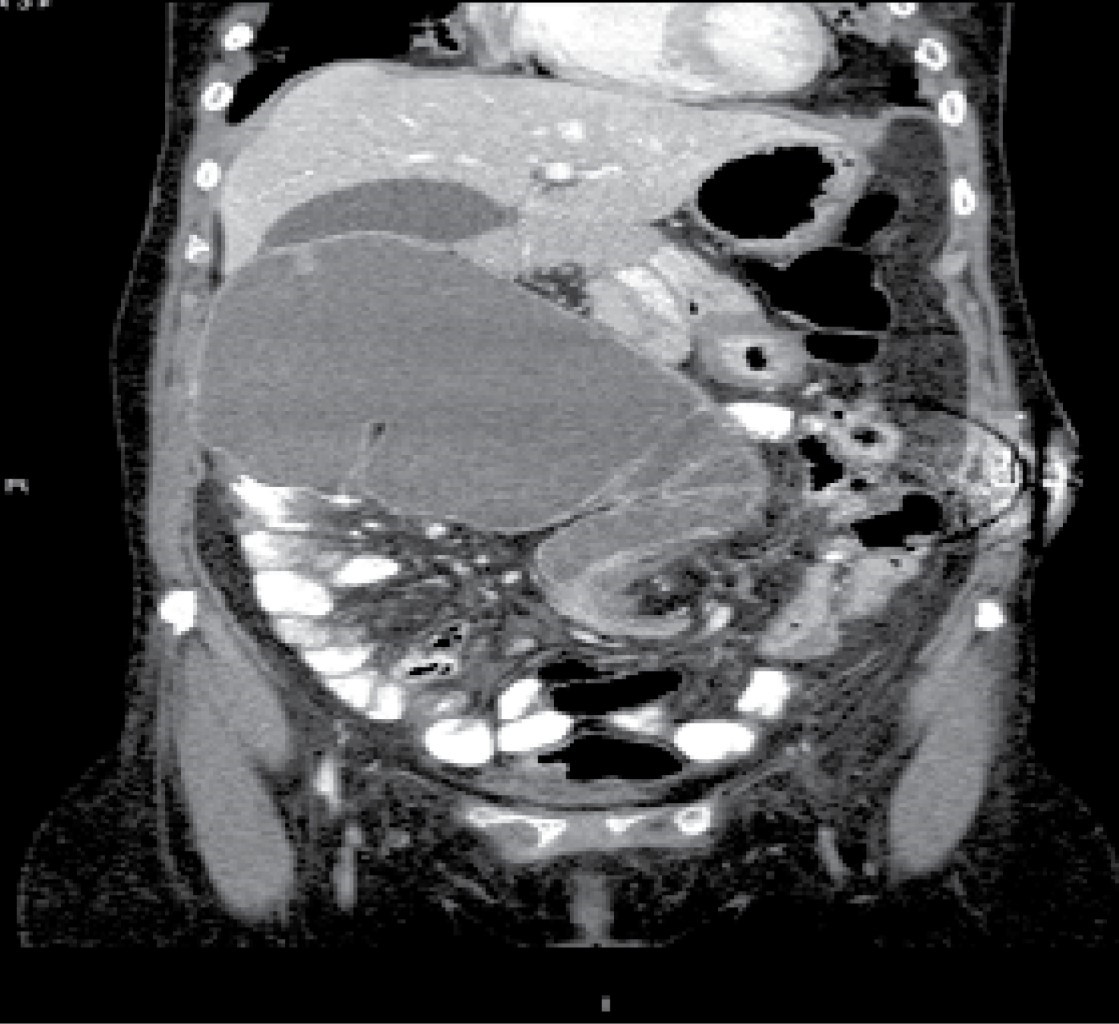

Laboratory studies were requested, which reported 12,000 leukocytes per cubic millimeter, seven-band forms, and serum lactate levels of 2.8 mmol/l. Subsequently, an abdominal tomography with double contrast was performed, finding significant cecal dilatation, the ascending colon and the proximal portion of the transverse colon, and a transition zone towards the distal third located in the left iliac fossa. Likewise, a supraumbilical abdominal wall hernia is found in the midline with scarce fatty tissue and omentum (Figures 1, 2, 3 and 4).

Figure 3